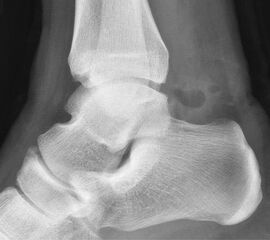

Reseziertes Os trigonum sowie prä- und postoperatives seitliches Röntgenbild nach arthroskopischer Entfernung eines Os trigonum.

• Bei Resektion von Osteophyten oder Entfernung eines Os trigonum postoperative seitliche Röntgenkontrolle des OSG.